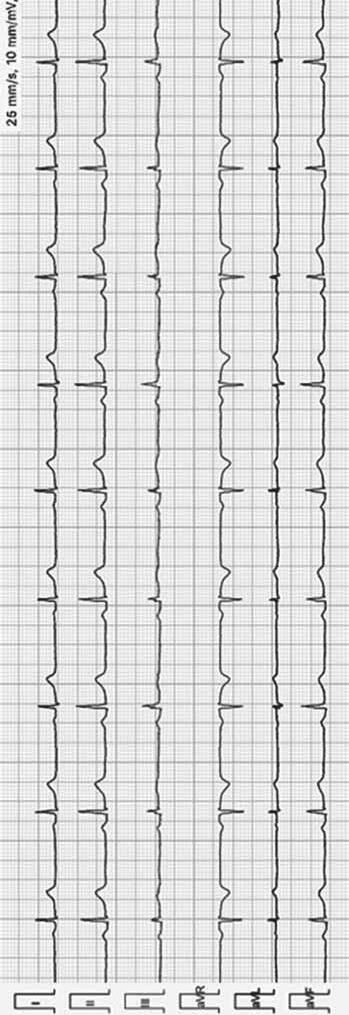

RYTM ZATOKOWY

Załamek P o morfologii +/–II, III, aVF

Rytm zatokowy > 100/min